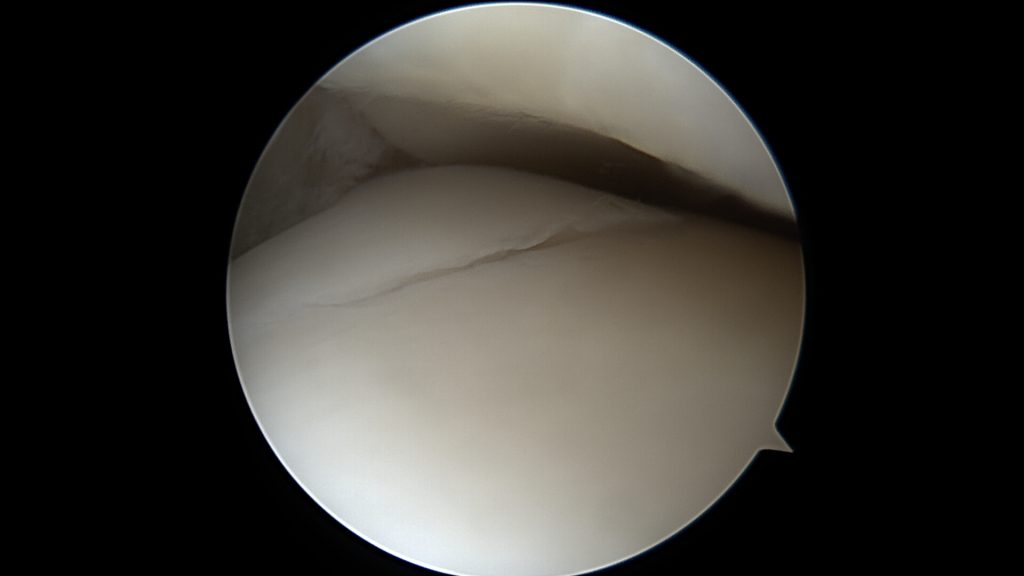

Chrząstka stawowa pokrywa powierzchnie ślizgowe w łożysku jakim jest staw. Jest to biała, lśniąca tkanka o trójwymiarowej budowie odpornej na zgniatanie oraz ścieranie. W stawie skokowym jest ona znacznie cieńsza niż w stawie kolanowym, jej grubość wynosi od 1 do 2 mm. Do uszkodzenia chrząstki stawowej dochodzi w momencie skręcenia stawu skokowego lub złamania dostawowego, powtarzających się obciążeń czy chorób jak np. reumatoidalne zapalenie stawów. Może też być ona uszkadzana wtórnie poprzez inne elementy stawu (np.: konflikt tkanek miękkich czy ciała wolne).

Uszkodzenia pełnej grubości chrząstki stawowej, punktowe wymagają leczenia operacyjnego. Nawet niewielkie pęknięcie chrząstki stawowej powoduje wtłaczanie płynu stawowego pod powierzchnie chrząstki oraz tworzenie się pod nią torbieli. Zwiększone ciśnienie oraz torbiele powodują następnie niszczenie kości oraz zapadanie się powierzchni chrzęstnej. Z czasem fragment chrząstki wraz z kością (uszkodzenie typu OCD) odrywa się i może przemieszczać się w jamie stawu.